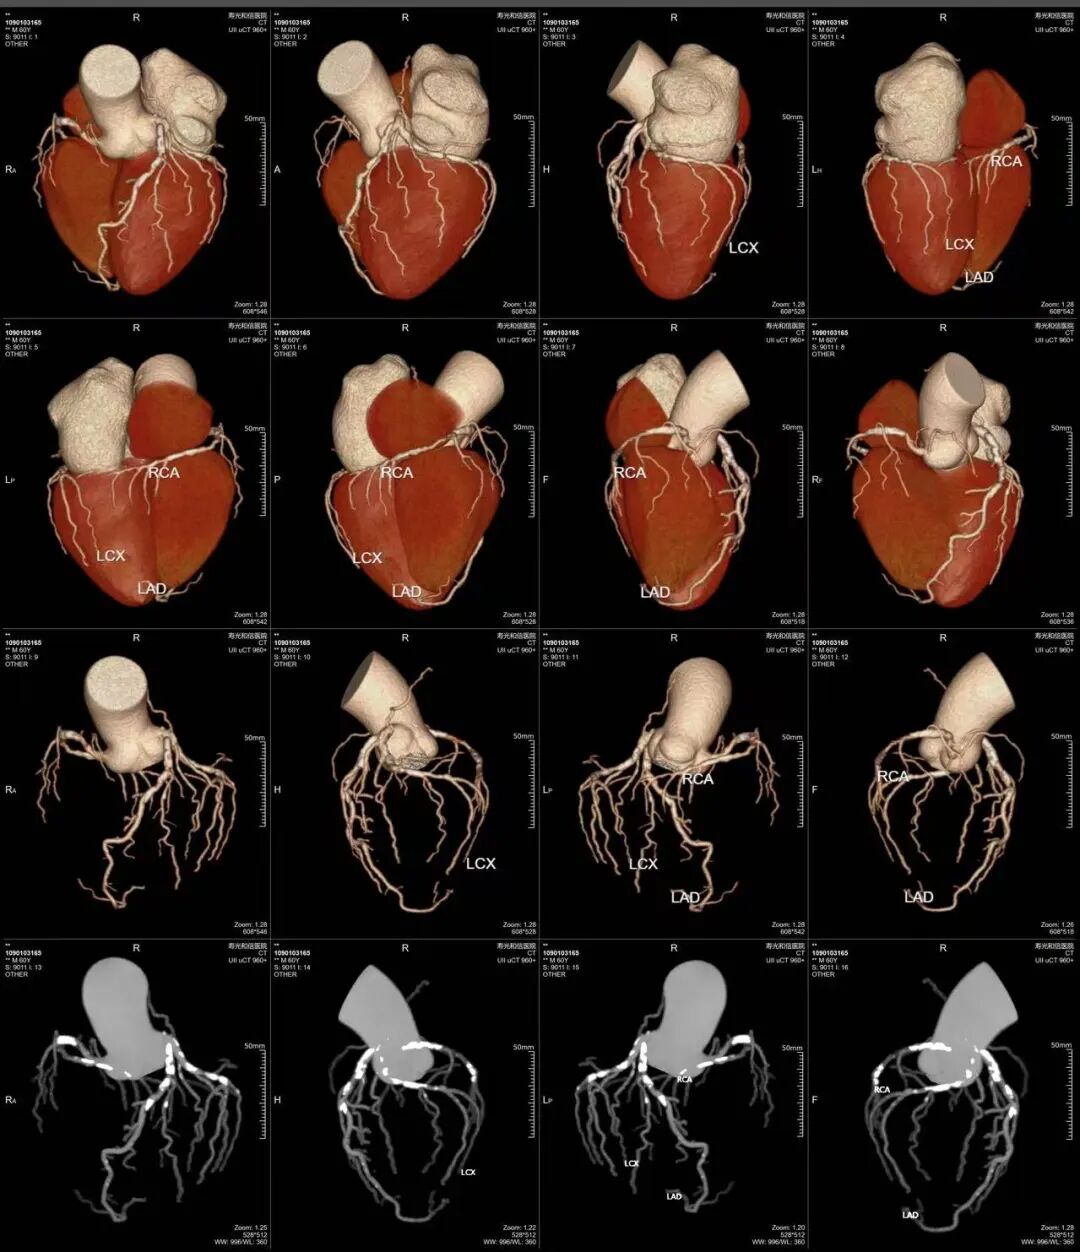

心脏搭桥术后

冠状动脉多发混合斑块形成并重度狭窄

冠状动脉和头颈部动脉联合成像

640层意味着扫描极薄、极细腻,冠脉上有没有斑块、斑块是什么性质、狭窄程度多少,看得一清二楚。钙化、软斑块、混合斑块,都逃不过它的“眼睛”。